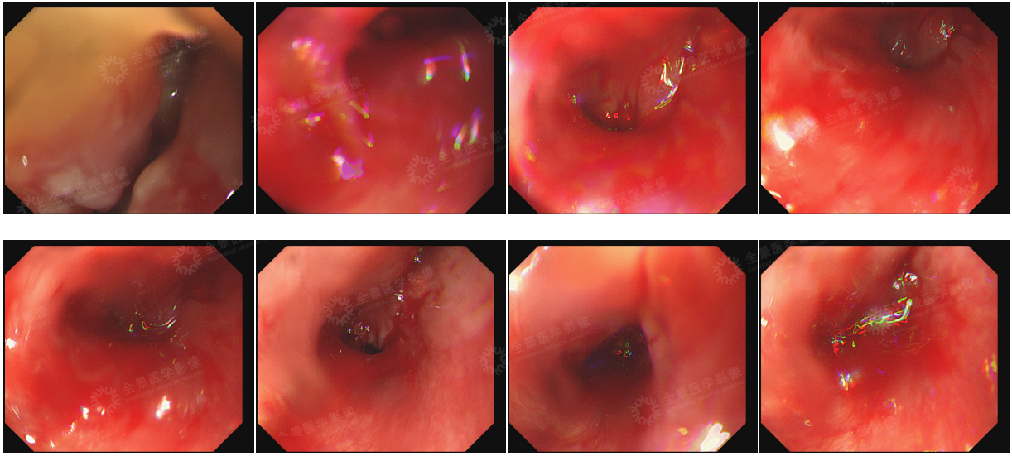

在胃镜刚进入食道上段离门齿 16 cm 处时,发现异常。杜主任现场快速评估后不排除继续操作可能引发大出血并堵塞气道可能,并初步判断为食道上段占位伴不完全性梗阻,在成功锁定病变位置后,中断检查,退出胃镜。

内镜所见:胃镜进入食道上段离门齿 16 cm 可见管壁狭窄伴不规则增生,食管腔大小约 5 mm,黏膜脆易出血。